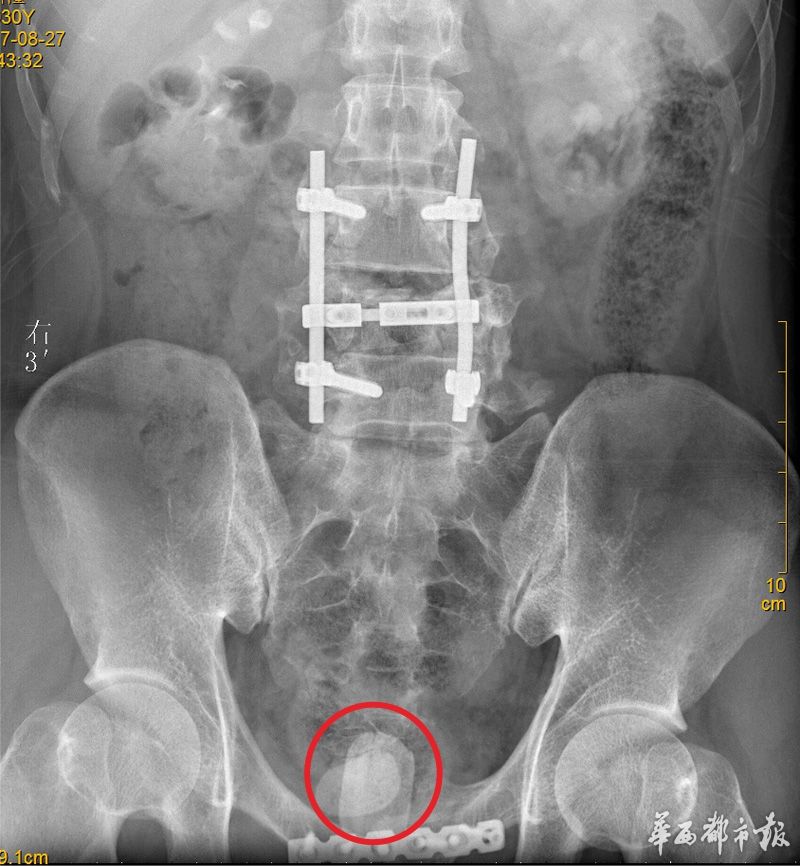

男子骨折去医院拍片意外发现膀胱内藏巨大结石当事人却表示不痛不痒

【资料】罕见膀胱巨大结石图片